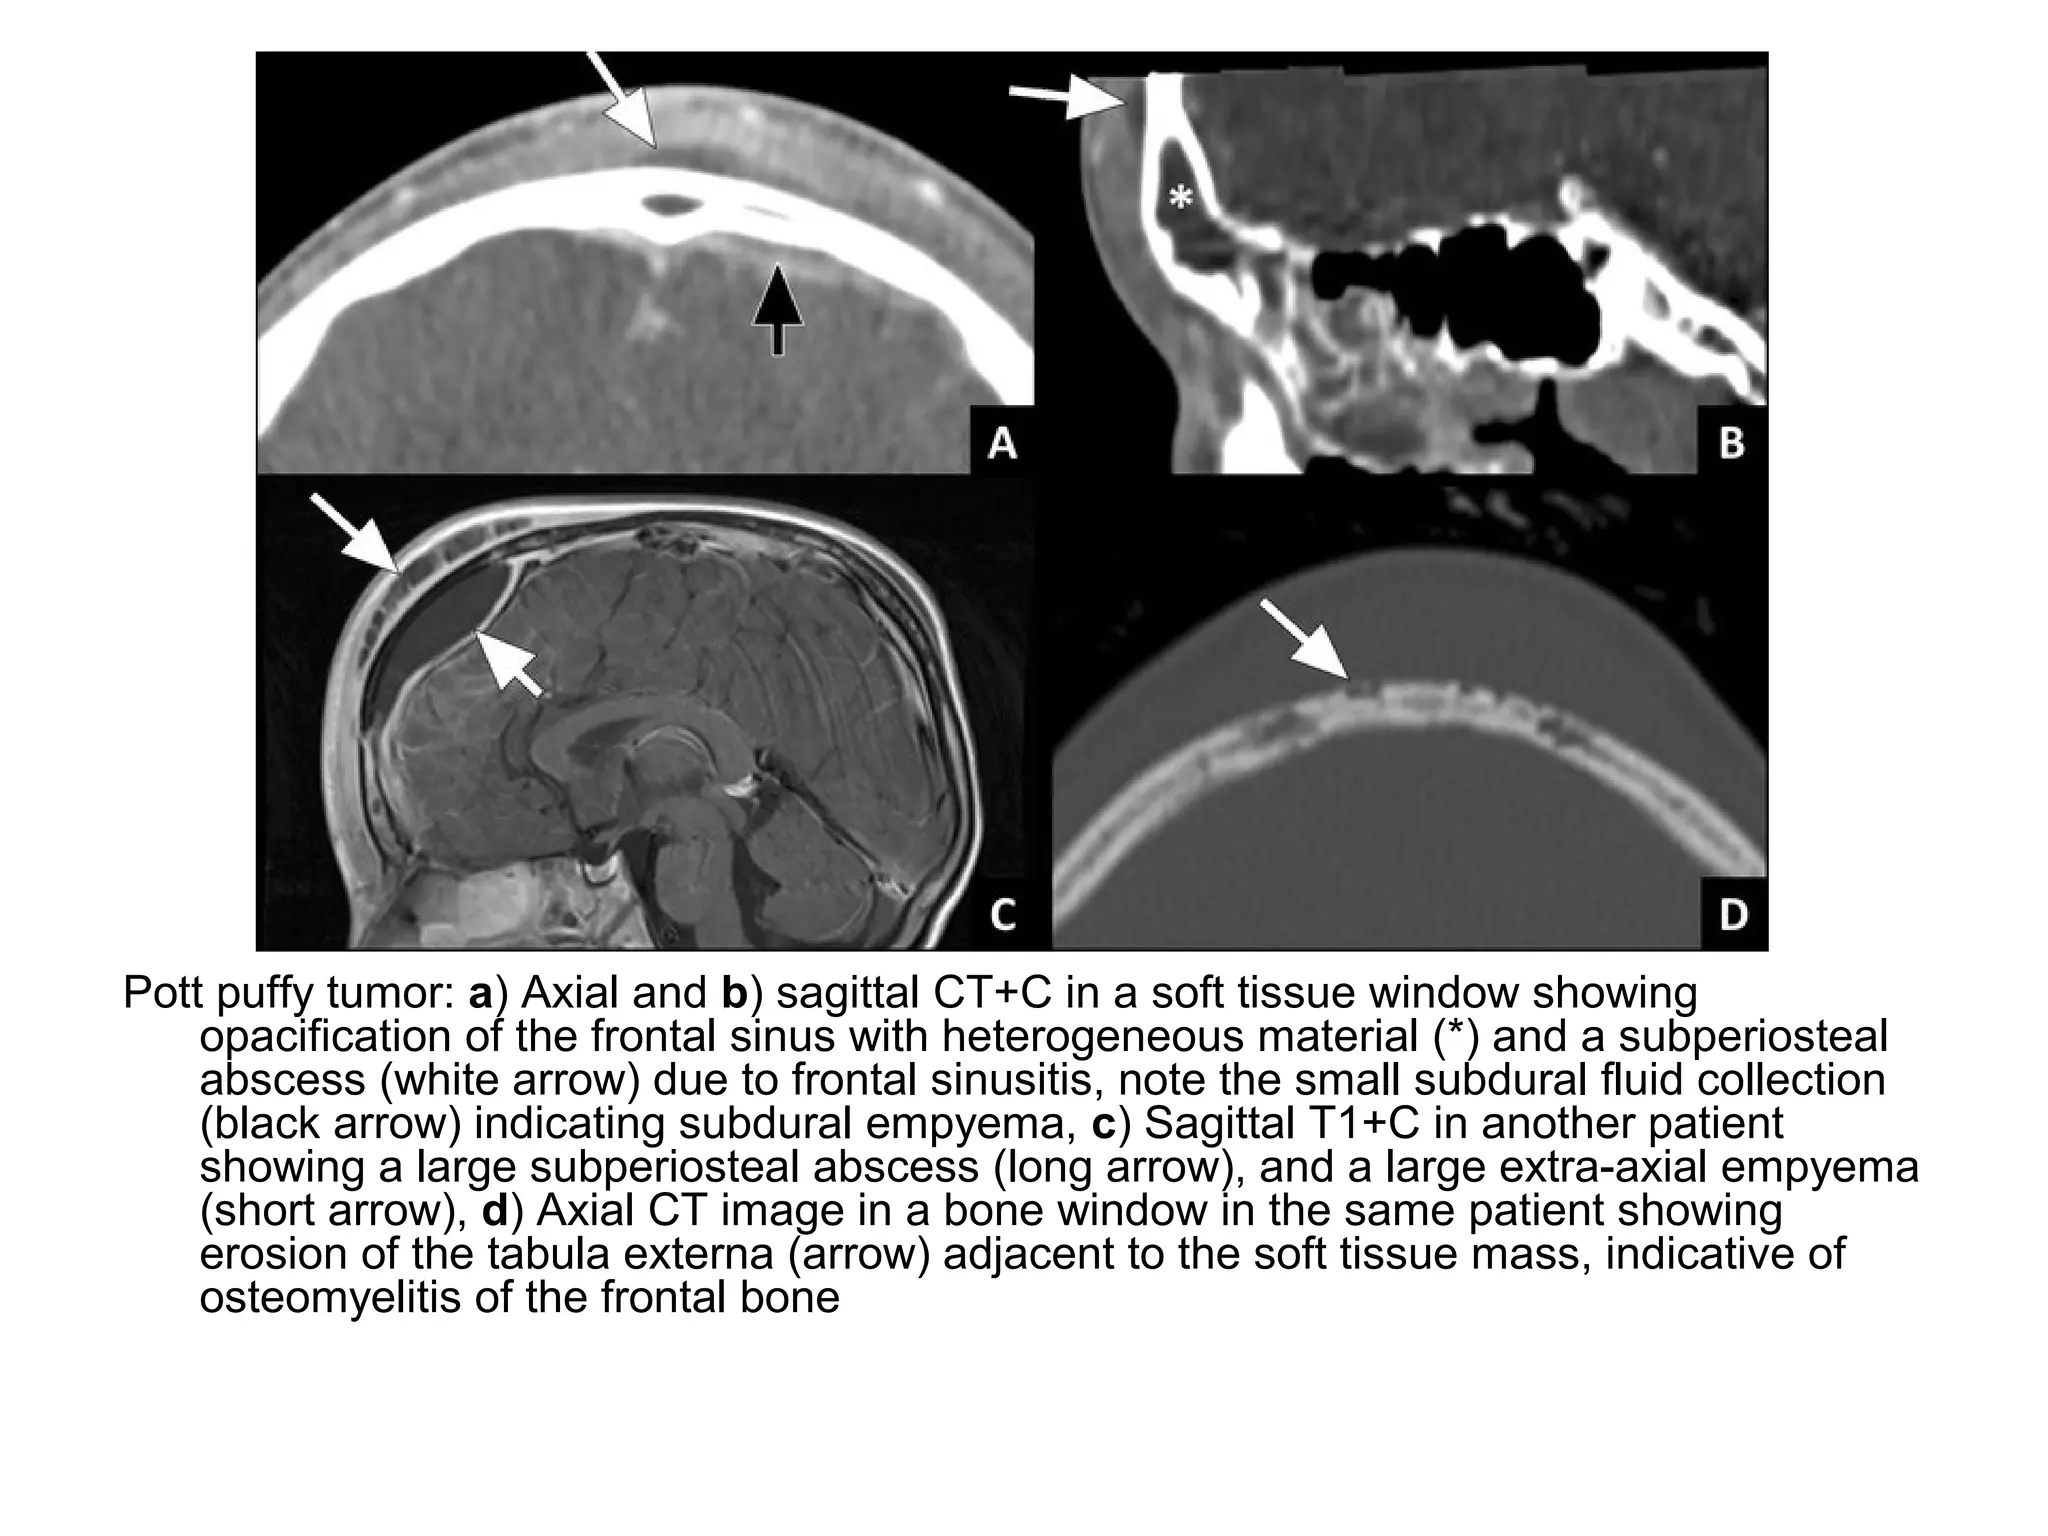

Pott puffy tumor: a) Axial and b) sagittal CT+C in a soft tissue window showing

opacification of the frontal sinus with heterogeneous material (*) and a subperiosteal

abscess (white arrow) due to frontal sinusitis, note the small subdural fluid collection

(black arrow) indicating subdural empyema, c) Sagittal T1+C in another patient

showing a large subperiosteal abscess (long arrow), and a large extra-axial empyema

(short arrow), d) Axial CT image in a bone window in the same patient showing

erosion of the tabula externa (arrow) adjacent to the soft tissue mass, indicative of

osteomyelitis of the frontal bone